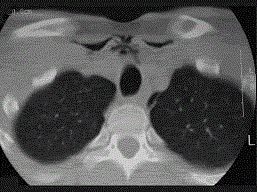

问题 27岁男性,开车外出在高速行驶时翻车,呼吸困难,喉部肿胀,CT检查如图所示,请选择正确的描述或诊断 ( )

选项 A、左侧杓状软骨骨折 B、考虑喉、气管破裂 C、左侧梨状窝软组织肿胀 D、颈部、胸骨下方软组织积气 E、左侧甲状软骨骨折

答案 BCDE